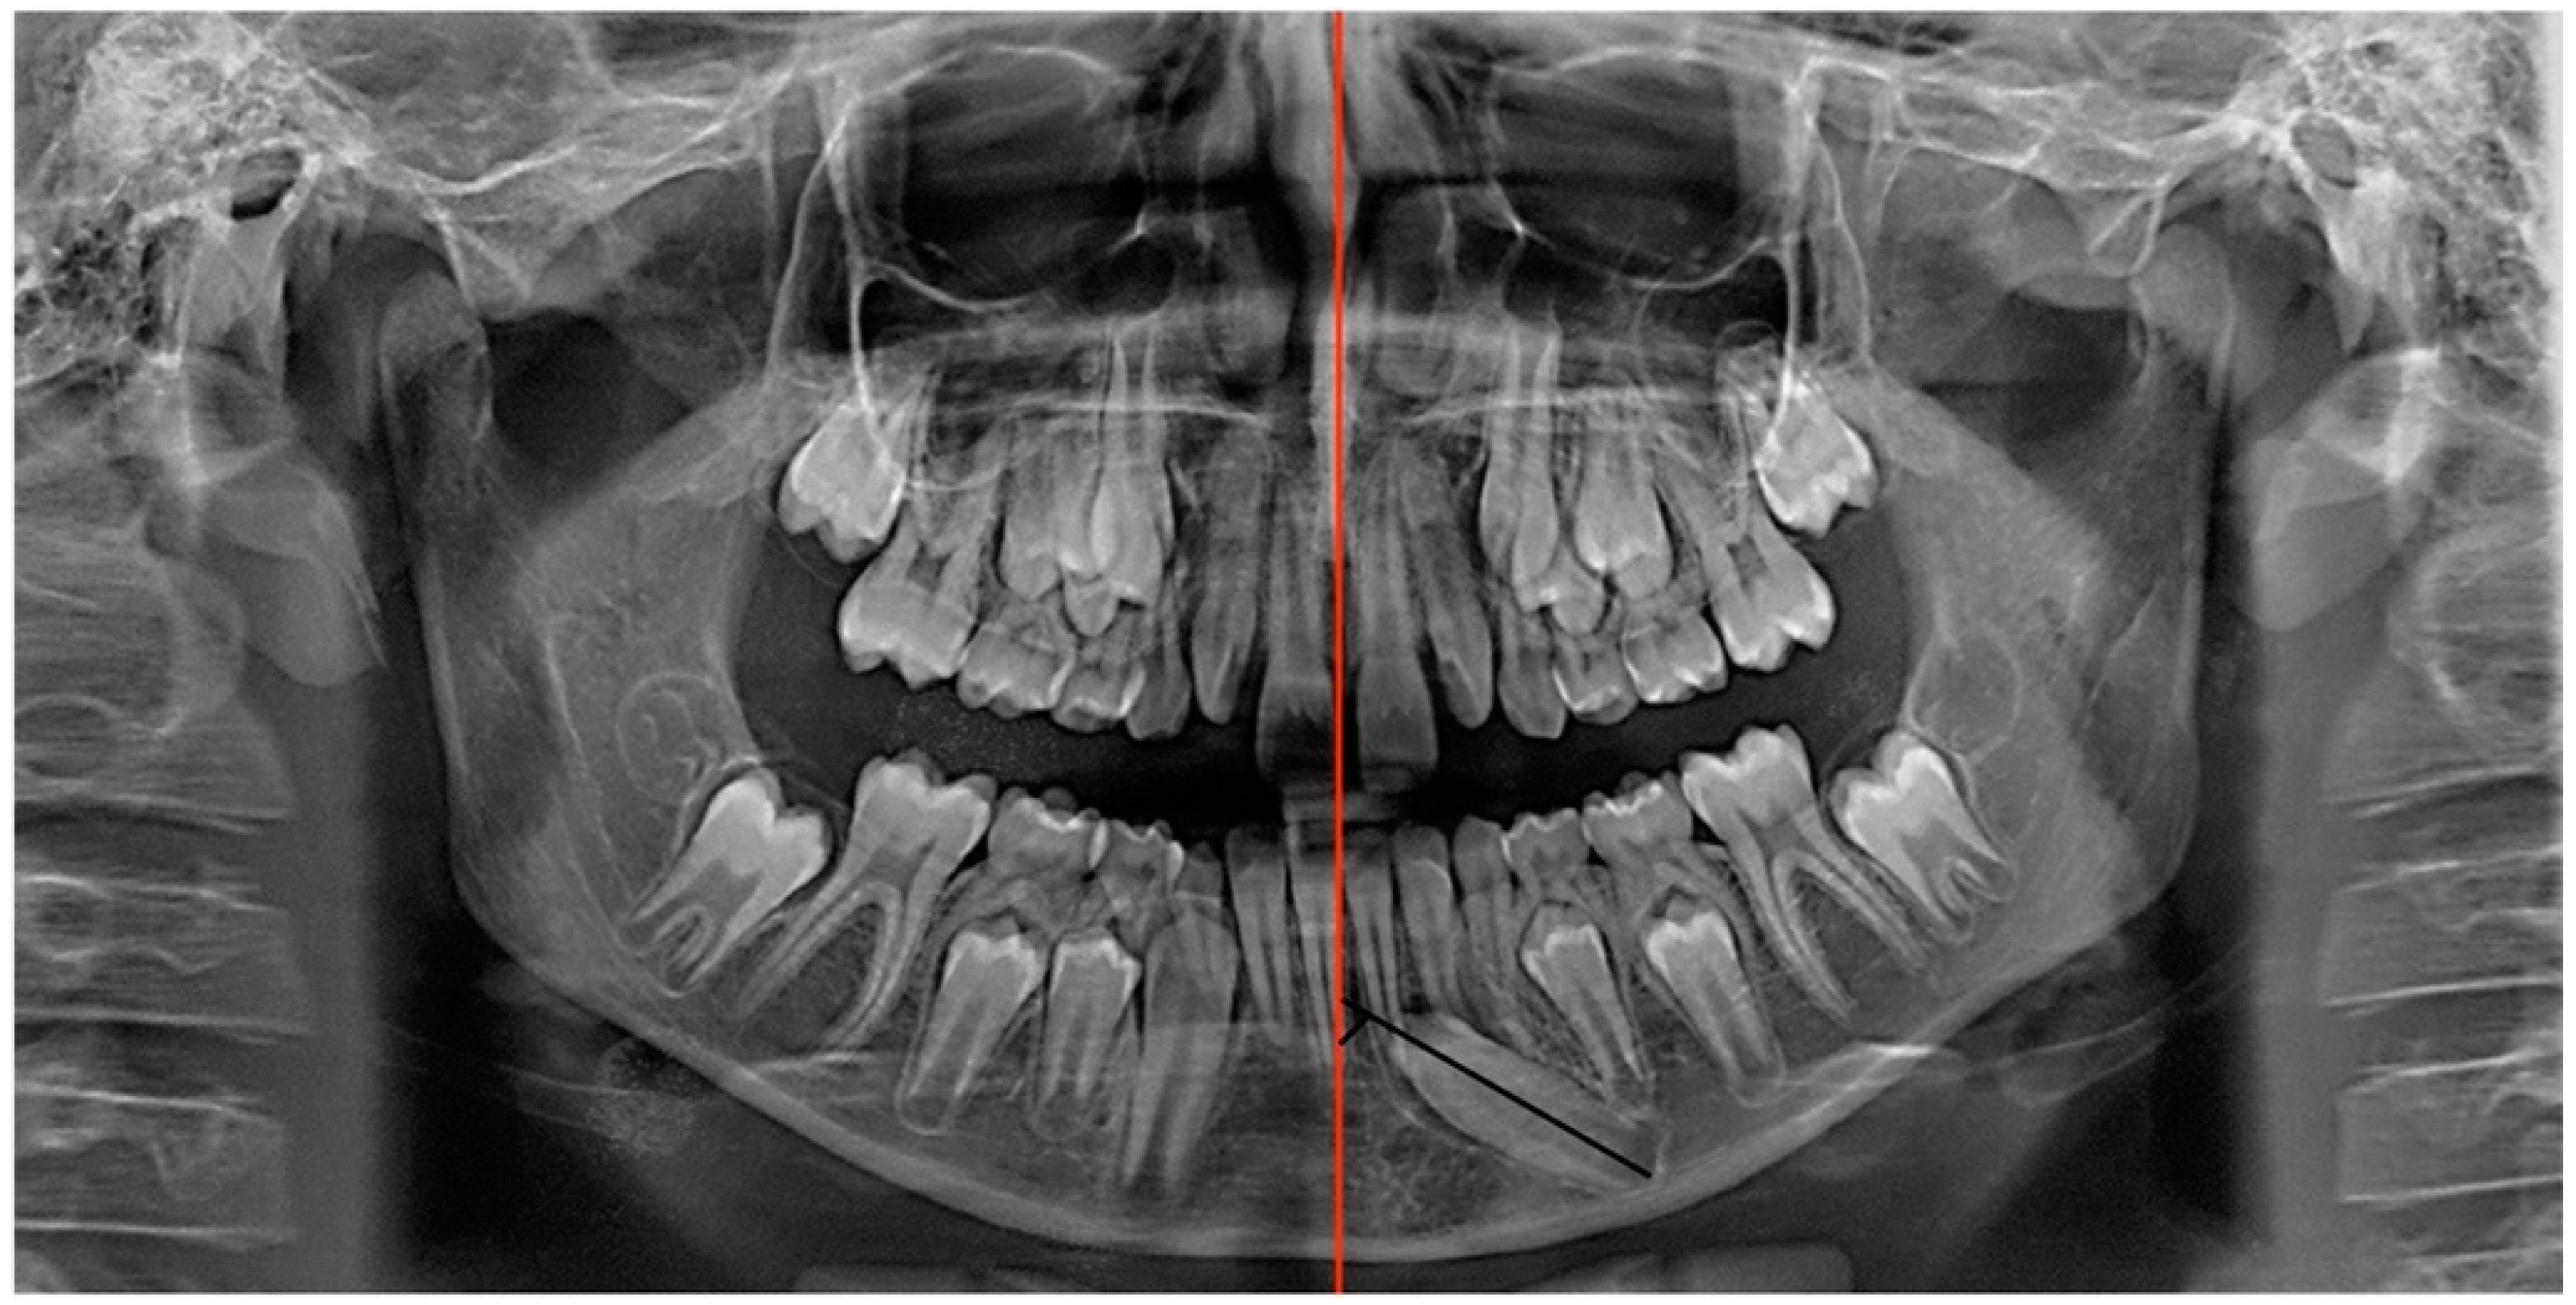

When the bracket attached to the traction element was visible through the gingiva after 8 months, the ipsilateral deciduous canine (element 7.3) was extracted and a gingivectomy was performed to place the button more apically on the crown to continue the traction (Figure 11 and Figure 12).

Figure 12. Panoramic radiography of treatment progress (1 year after the first panoramic radiograph).